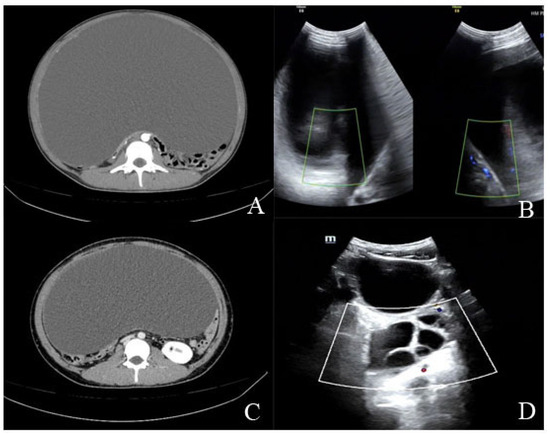

2.1.2. Diagnostic Workup

2.2.2. Diagnostic Workup

| Imaging findings | Large ovarian cystic mass with a maximum diameter of about 35 cm | Large ovarian cystic mass with a maximum diameter of 43 cm |

| Recurrence of the ovarian cysts after surgery | Yes | Yes |